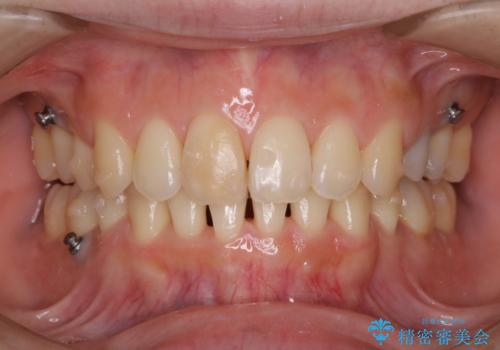

- 着色を落としてほしいとのことで来院されました。

PMTC60分コースを行いました。

その際は、仕方がないので出来るだけ早くマウスピースを洗い、歯磨きをすると着色がつきにくくなるため、意識してやってみてください。